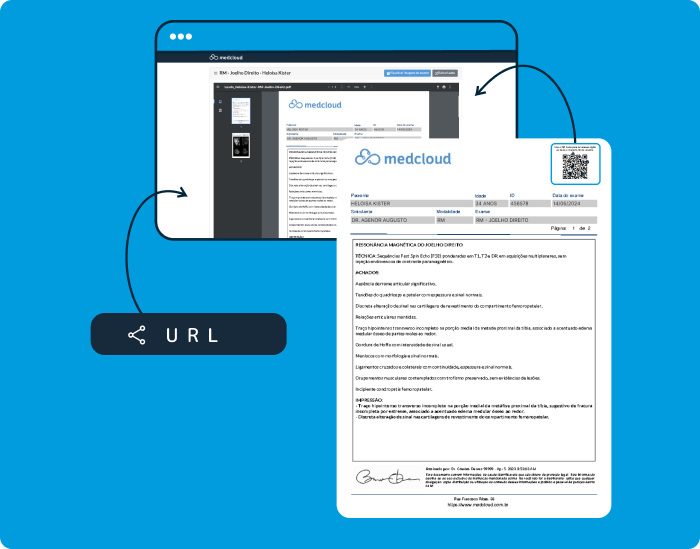

Simple y ágil a través de correo electrónico y WhatsApp para el acceso de sus pacientes y médicos solicitantes.

Garantice el acceso a los resultados para cualquier perfil de paciente. Comparta los resultados de sus exámenes fácilmente a través de un código QR o un enlace de acceso, incluso sin la aplicación y sin necesidad de iniciar sesión o contraseña.

Acceda a imágenes, informes y archivos adjuntos en su teléfono inteligente. Notificar a los pacientes y solicitantes cuando haya un resultado disponible. Consulte sus resultados desde 1 solo link.